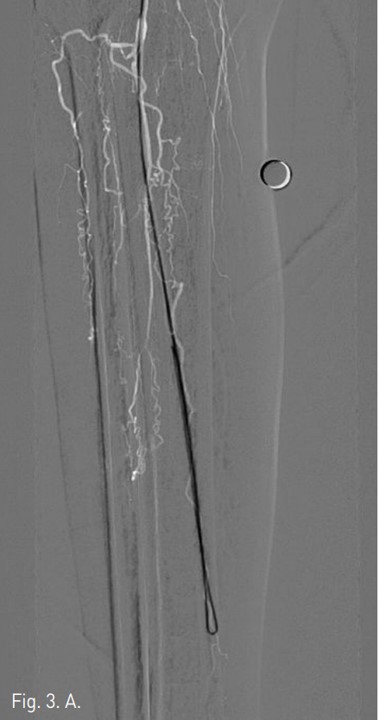

Fig. 3. A

Fig. 3. A. A U-looped wire tip is passed along the subintimal channel of occluded left peroneal artery.

일단 후경골 동맥은 그대로 두고, TP trunk에서 0.016 inch guide wire(GT guide wire, Terumo, Japan)을 사용하여 막혀 있는 비골동맥의 입구에서 subintimal guide wire passage한 다음 (Fig. 3A) 비골동맥의 원위부 true lumen으로 re-entry가 되었다. 3mm/10cm long balloon (SAVVY, CORDIS, Miami, USA))으로 우측 비골동맥 에 대해 subintimal angioplasty를 시행하였으며 우측 비골동맥의 혈류는 재개통 되었다 (Fig. 3B).